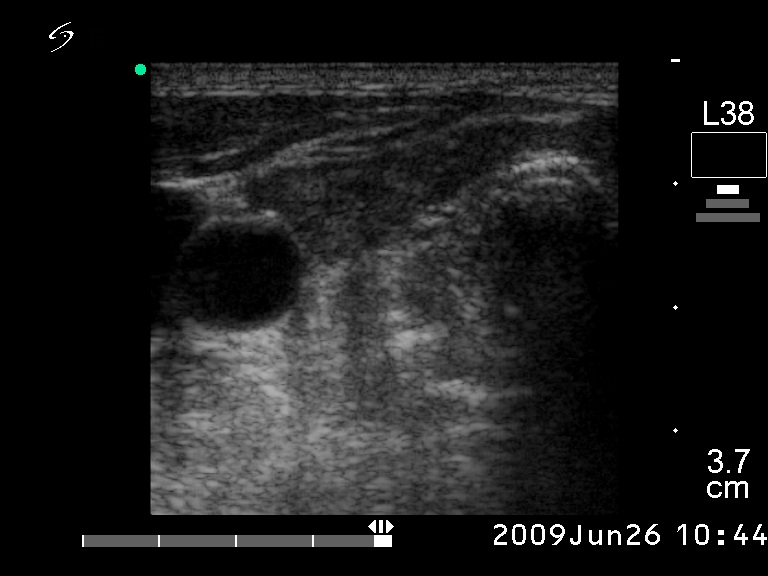

Ultrasonography. The right lobe was hypoechogenic and was not enlarged. The pattern in this lobe corresponded to Hashimoto's thyroiditis. There was a huge tumor in the left thyroid. The pattern of the left lobe varied from moderate to severe hypoechogenicity. The tumor was avascular.